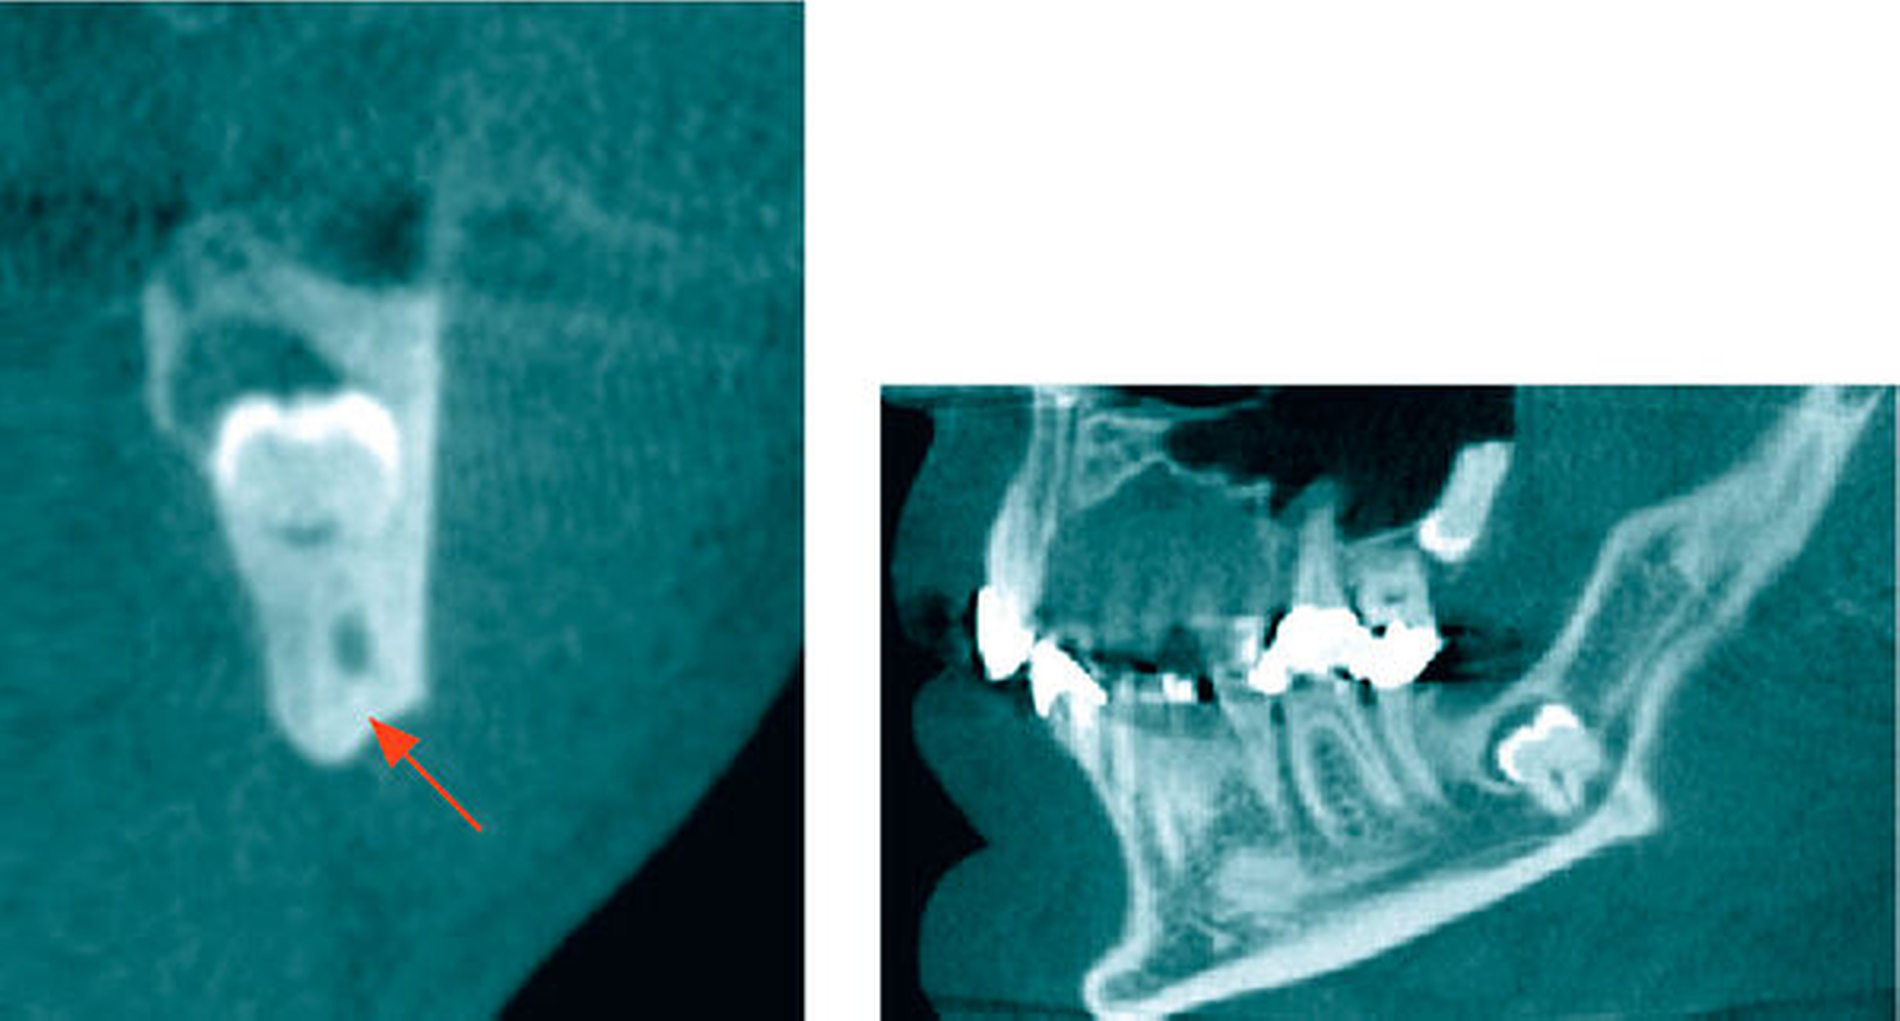

In der koronaren und der sagittalen Schicht des DVT zeigte sich deutlich die Lage beider Apices in der kaudalen Kompakta des Corpus mandibulae. Zudem wurde ein intraradikulärer Verlauf des Canalis mandibularis rechts durch die Wurzeln des 48 (Abbildung 2) erkannt. Am ebenfalls tief retinierten Zahn 38 konnte relativ zur Wurzel des Zahnes 38 ein lingualer Verlauf des Canalis mandibularis verifiziert werden (Abbildung 3).

Zur Abklärung der Lagebeziehung des 38 zum N. alveolaris inferior und relativ zum Unterkieferrand sowie zur Abklärung der Verlagerung des 28 beziehungsweise des Zustands der Kieferhöhle links wurde eine DVT durchgeführt. Dabei zeigte sich, dass der Nervkanal zwischen den vestibulär und lingual in der Unterkiefer-Kortikalis endenden Wurzeln des tief vertikal verlagerten Zahnes 38 verlief. Der Zahn 28 wurde mit Kronenbeginn kranial im apikalen Wurzeldrittel des Zahnes 27 vertikal verlagert dargestellt (Abbildung 7).